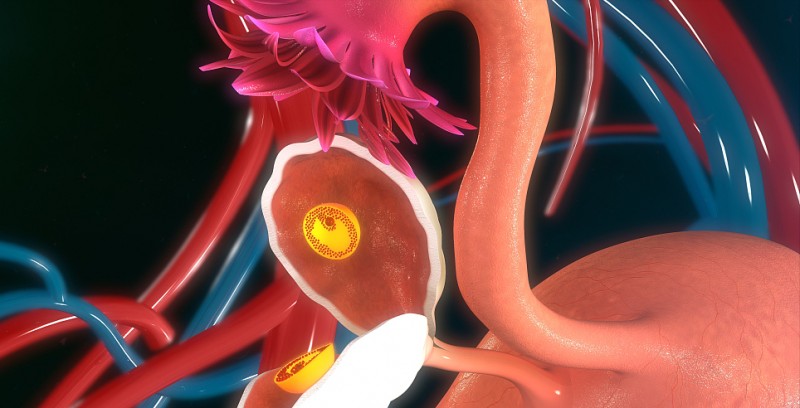

子宫输卵管造影是一种用于评估女性不孕症的专门放射学程序,其目的是评估子宫腔和输卵管的形状和功能。子宫输卵管造影涉及使用荧光透视,一种实时使用的X射线技术可视化体..

现在由于输卵管阻塞而导致不能怀孕的女性越来越常见,其中的原因有很多,所以有很多的不孕患者选择输卵管造影手术,那么,什么是输卵管造影呢?什么是输卵管造影: 输卵管..

输卵管造影用于检查输卵管通畅与否,这是临床应用最为广泛的检查手段之一,不仅仅了解输卵管是否通畅,而且也能知道输卵管堵塞部位和宫腔形态。相对来说损伤小,能对输卵管..